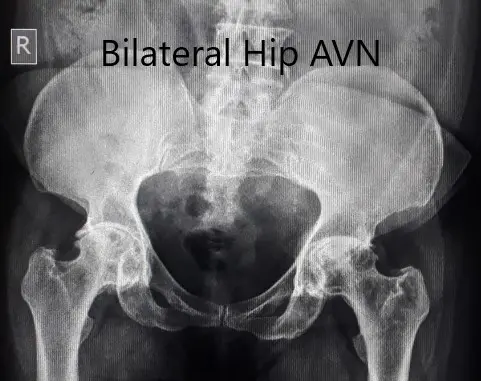

Preoperative X-ray of the pelvis in anteroposterior view.

An X-ray was obtained which suggested a deformed head of femur bilaterally. There were features of arthritis bilaterally with joint space reduction, sclerosis, subchondral cysts, and osteophytes bilaterally.